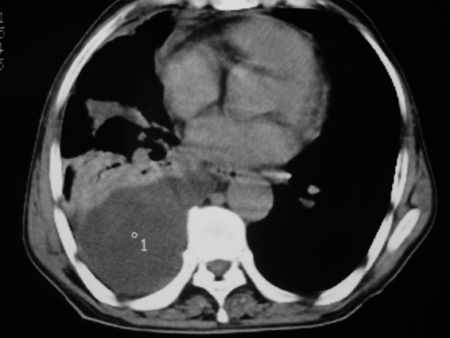

男77岁,胸痛就诊

右侧胸腔积液,部分包裹,右下肺膨胀不全,右下肺感染。

考虑右肺门占位并下叶不张 右胸包裹积液

右肺中叶及下叶炎症并胸腔积液(部分包裹),建议抽液后复查ct除外占位。